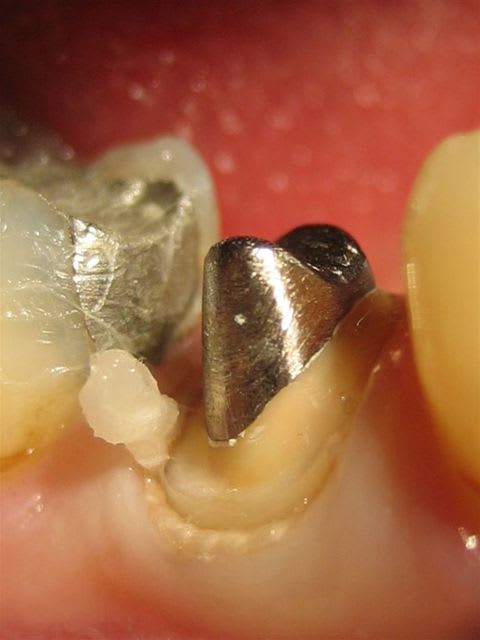

Si on ne voir rien en bouche le prothesiste ne peut pas faire de miracle !

Plus la limite est visible et moins il y a d'échec;

Depuis deux mois j'utilise des fraises "à téton" qui sont en fait des fraises à congé moyen, voire large, et avec un petit téton mousse à la pointe. Je glisse ce téton dans le sulcus et en voiture simone, j'ai un congé moyen harmonieux sans problème tout autour, économie tissulaire garantie.

La fraise L1 sert à passer les points de contact, mais en rien elle ne permet de marquer une limite !!!